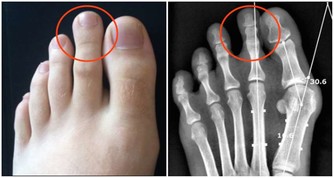

沒有屁放:疾病信號如果長時間不放屁,說明問題嚴重。新生兒不放屁,要檢查是否為無肛症或肛門發育不全。大人沒有屁放,腹部發脹如鼓,說明腹部脹氣,這就要考慮肛門直腸是否有毛病,如炎症、腫瘤、便秘、痔瘡等,必要時需肛門插管排氣。患有腸套疊、腸扭轉、腸梗阻無屁,是因為屁被腸子堵住。

▲如果無屁放出並伴有劇烈的腸絞痛者,必須緊急到醫院求治,作為急診進行搶救處理。此外,胃穿孔、闌尾炎穿孔形成的腹膜炎,腹部發硬,觸之劇痛,也可無屁。